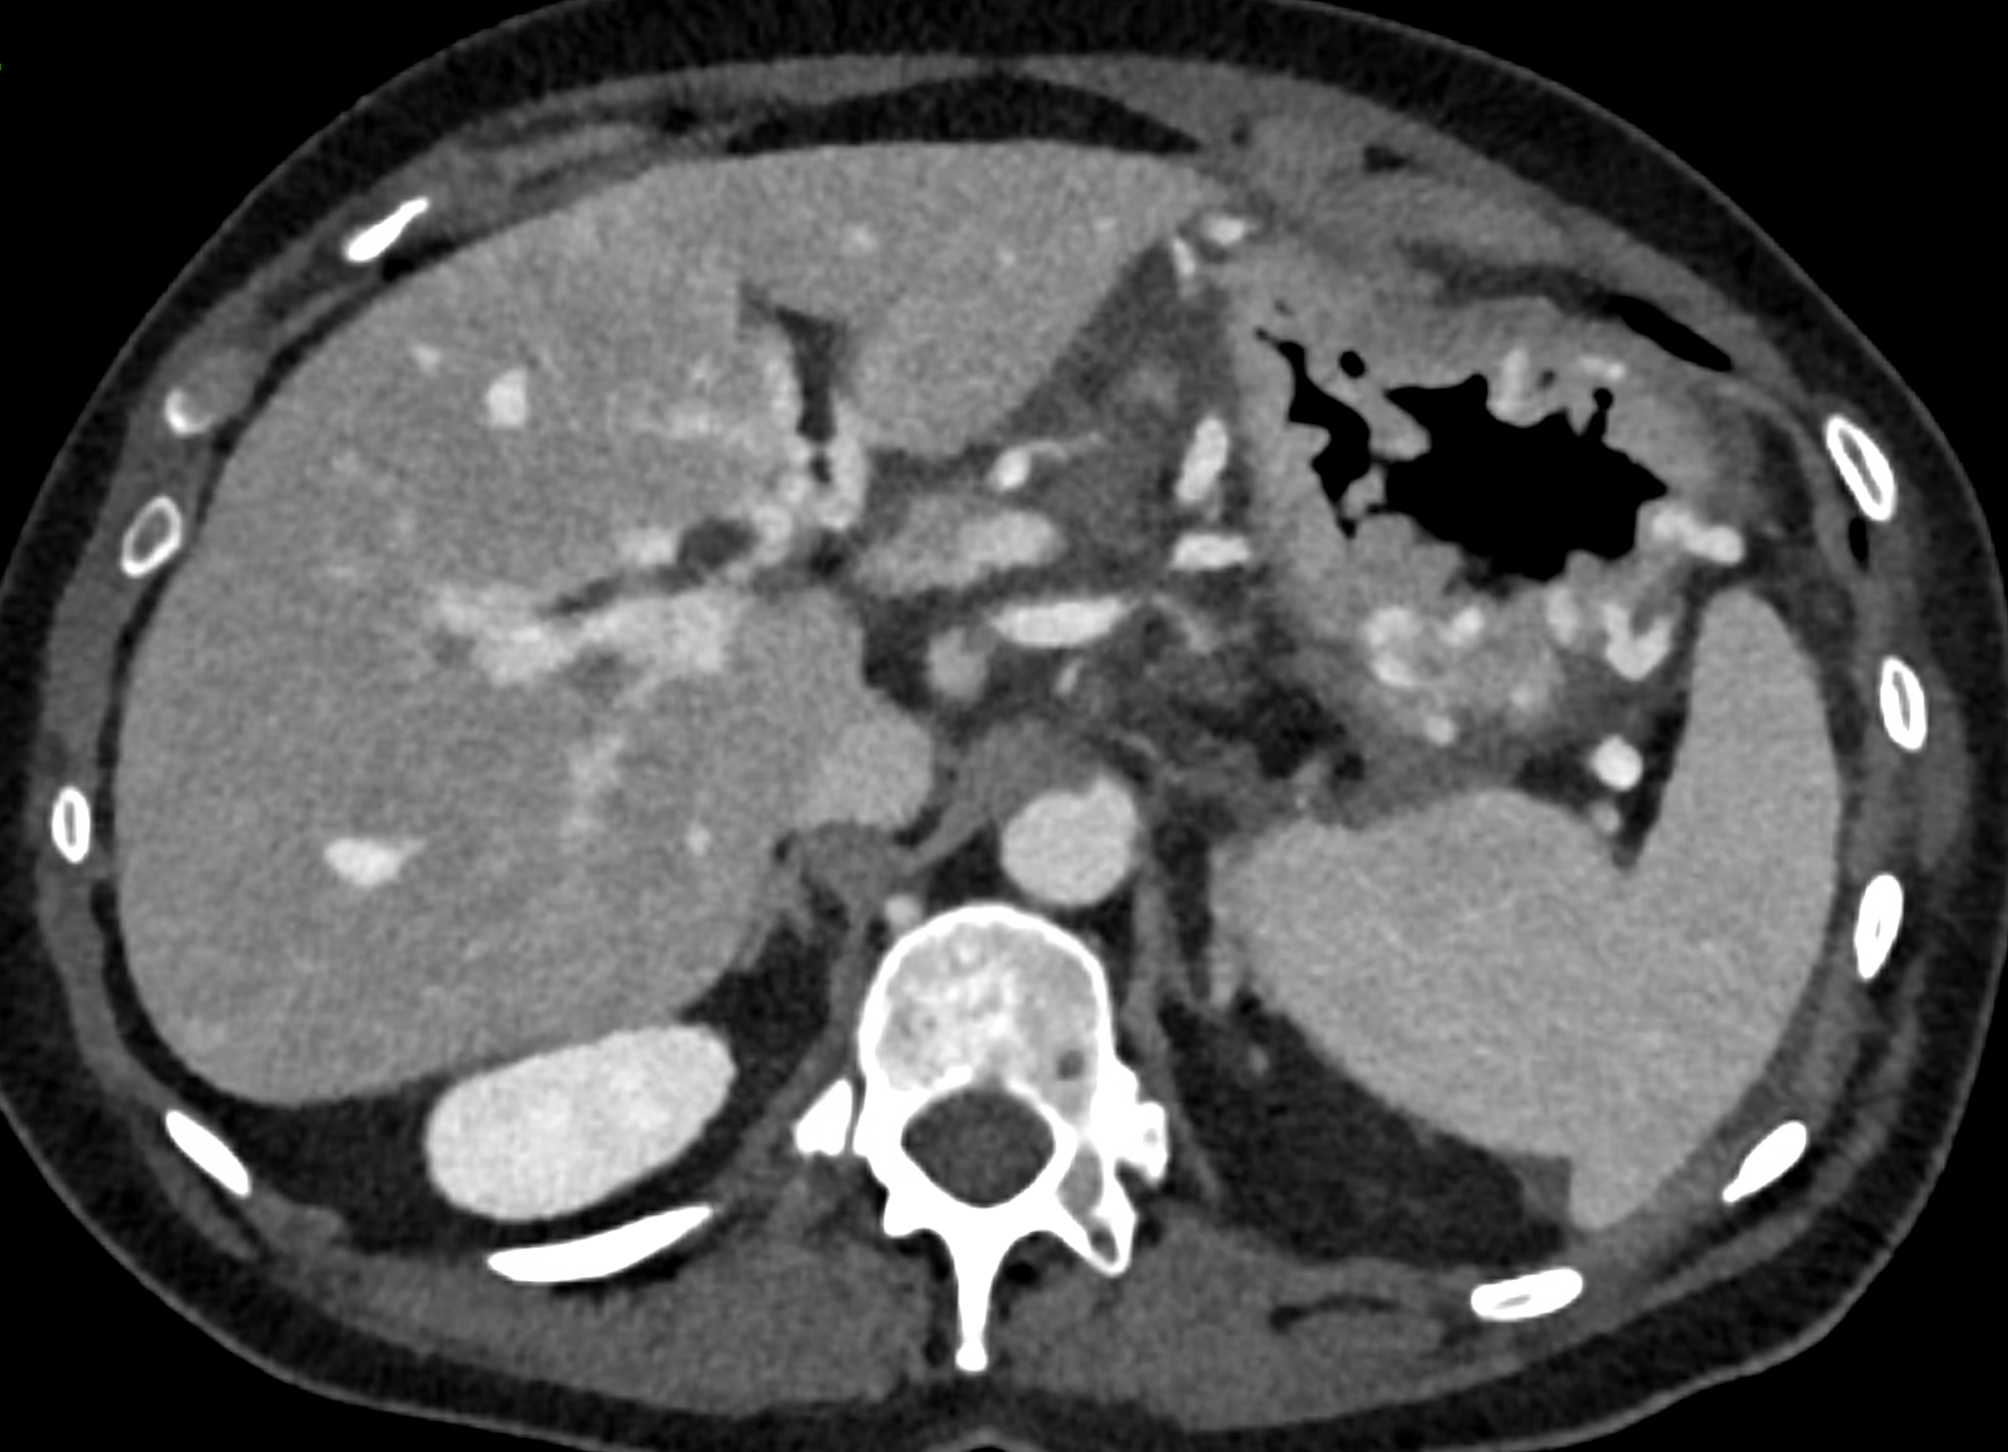

A patient with chronic pancreatitis and chronically occluded portal vein. The bile ducts have a significantly dilated wall, from the trunk, through the stump of the cystic duct, to the right and especially the left branch of the hepatic duct. At the same time, a large pseudocyst in the pancreas, dilatation of the pancreatic duct, and chromic occlusion of the superior mesenteric vein, splenic vein, and portal vein trunk are evident. Along with portal biliopathy, there is also arixy of the cardia and esophagus, as well as cavernous remodeling of the portal circulation itself.

dilated veins in the wall of left hepatic duct

dilated veins in the wall of left hepatic duct and paralel veins of portal cavernous transformation